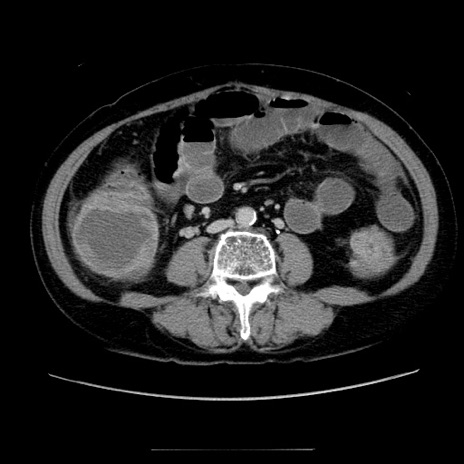

症例5(横断像)

【症例】70歳代女性

【主訴】お腹が張る

【現病歴】1週間くらい前から腹部膨満の自覚あり。昨日夜から増悪したため、本日救急外来受診。

【身体所見】意識清明、BT 36.5℃、BP 165/106mmHg、HR 80bpm、SpO2 98%、腹部:膨満、軟、自発痛・圧痛なし、触診にて不快感あり、腸蠕動音:減弱

【データ】WBC 12600、CRP 1.04